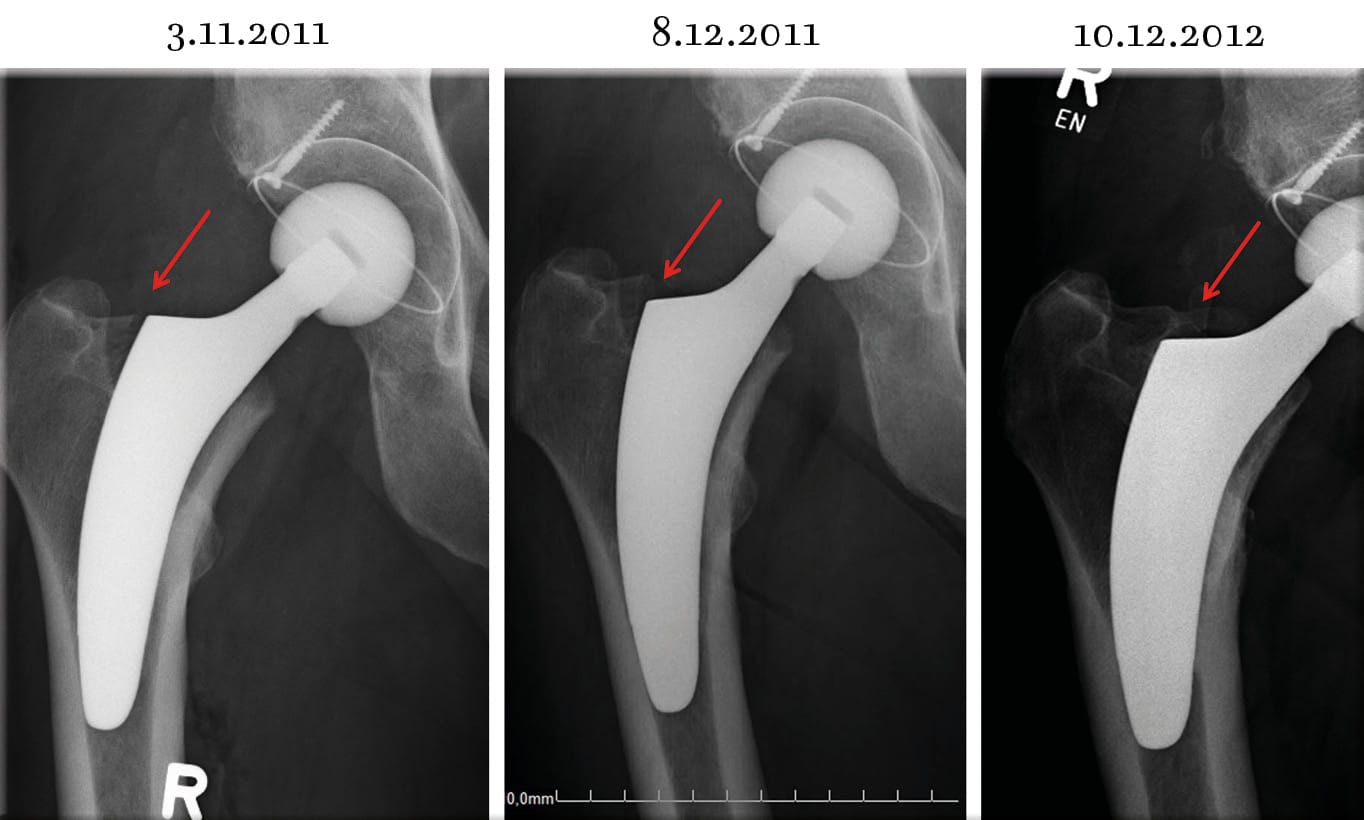

Weight limits for implants are not often expressed by the manufacturer. Especially with short stems surgeons are skeptic to use them with heavy and obese patients. We took part in a multi-center study in which the stem “optimys” (Figure 1) was used that follows the calcar and slips into the femur easily. 483 patients were divided into 3 groups with body mass index (BMI) <25, 25-30, >30. After 24 months there were no statistically significant differences between these groups respective the implant. As also can be seen in standard implants there were very few subsidences in all three groups up to 6mm during the first three months mainly because the chosen implant was too small partly due to the learning curve with this new implant. Later on during the follow up the implants were stable and no more subsidence was evident (Figure 2).